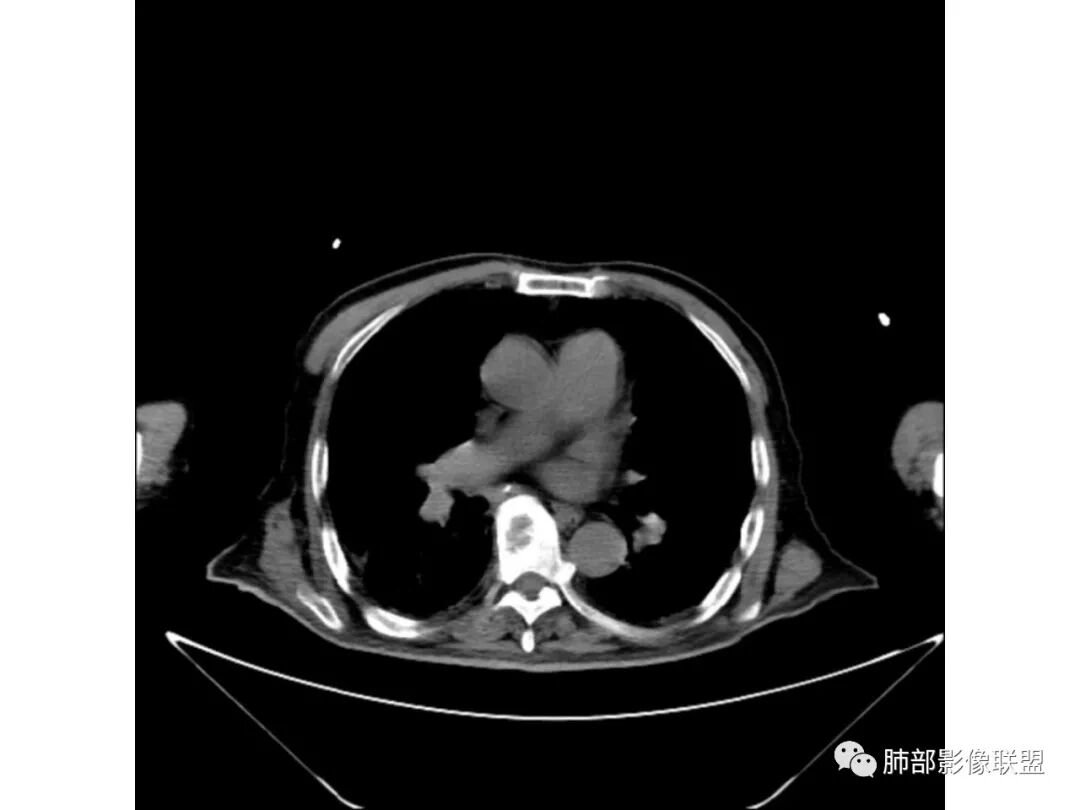

老年男性,既往糖尿病10年,右上肺不均匀实变+两肺实质及间质病变;本例良性感染性病变支持点:糖尿病史+双肺多发的实变,右上肺实变内可见支气管气像;恶性支持点:实变内的支气管似乎呈“枯树枝”样改变,纵隔有超过1.5cm的肿大淋巴结。

个人倾向良性感染性病变>恶性;考虑双肺混合性感染,右肺上叶实变拟结核可能性大,重点鉴别是弥漫浸润性肺腺癌。建议纤支镜检查。

老年男性,咳嗽气喘10天,双肺明显肺气肿,右上肺叶实变,内见大量空洞及囊腔样改变(部分为支气管扩张),实变区周围表现为网格样改变,有明显的小叶间隔增厚,边界似清非清,支气管走行僵硬,有枯树枝样改变,双下肺胸膜下小叶间隔增厚明显,边缘相对模糊,综合考虑如下:1、粘液腺癌可能大(枯树枝样改变,边界似清非清,小叶间隔增厚符合)。2、结核,右上肺似像干酷样改变,内有空洞及支扩样改变支持,但下肺及左肺无相关支气管播散的小叶中心结节及树芽,不支持,临床病症不支持,只有咳嗽,喘气,无咳痰及结核中毒症状。当然结核是妖,需要结合痰检及结核相关指标进一步明确。3、肺克,虽有10年糖尿病史,但肺部只有右肺改变明显,无胸膜下脓肿表现,无脓毒栓表现,临床症状也不支持。4、其他感染?双下肺胸膜下病灶边缘模糊,不完全除外,需要结合临床炎性指标分析。

总体分析就是不符合恶性。蜂窝、空洞与肺气肿有关,支气管主要还是远端稍扩张

肺炎型肺癌——支气管远端狭窄或堵塞为主

外围的支气管不会这么大,而且越到远端越小,这个不符合,所以考虑稍扩张

单发在右上叶,好发的病变:结核、肺克雷白杆菌。

支气管、内部的小囊腔,部分无壁小空洞,病灶部分边界偏清,支持结核